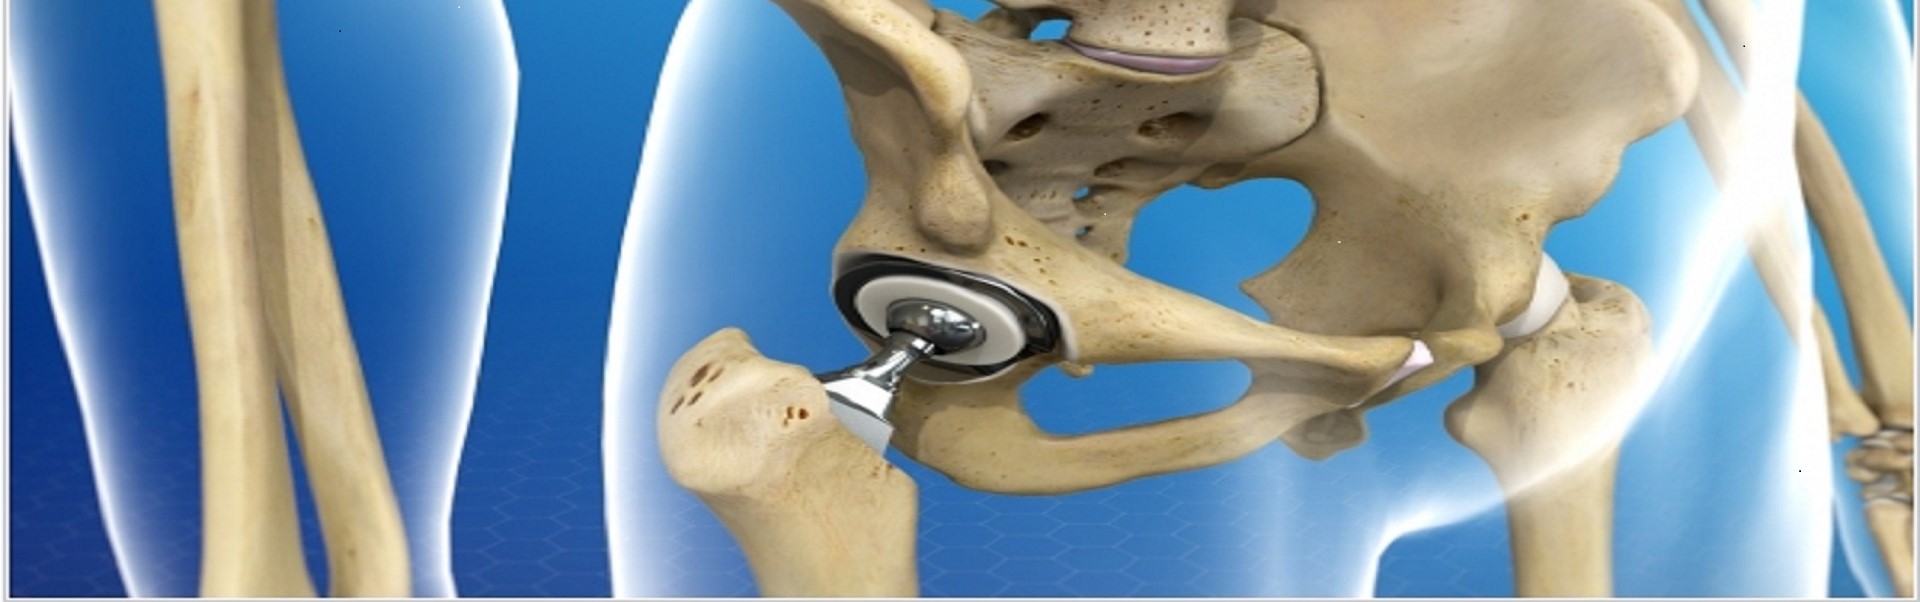

• Ендопротезування кульшового суглобу

Ендопротезування кульшового суглобу

Если постоянная боль в тазобедренном суставе мешает выполнять самые простые повседневные движения, нарушает ритм нормальной жизни, Вам необходимо обратиться за консультацией к специалисту ...